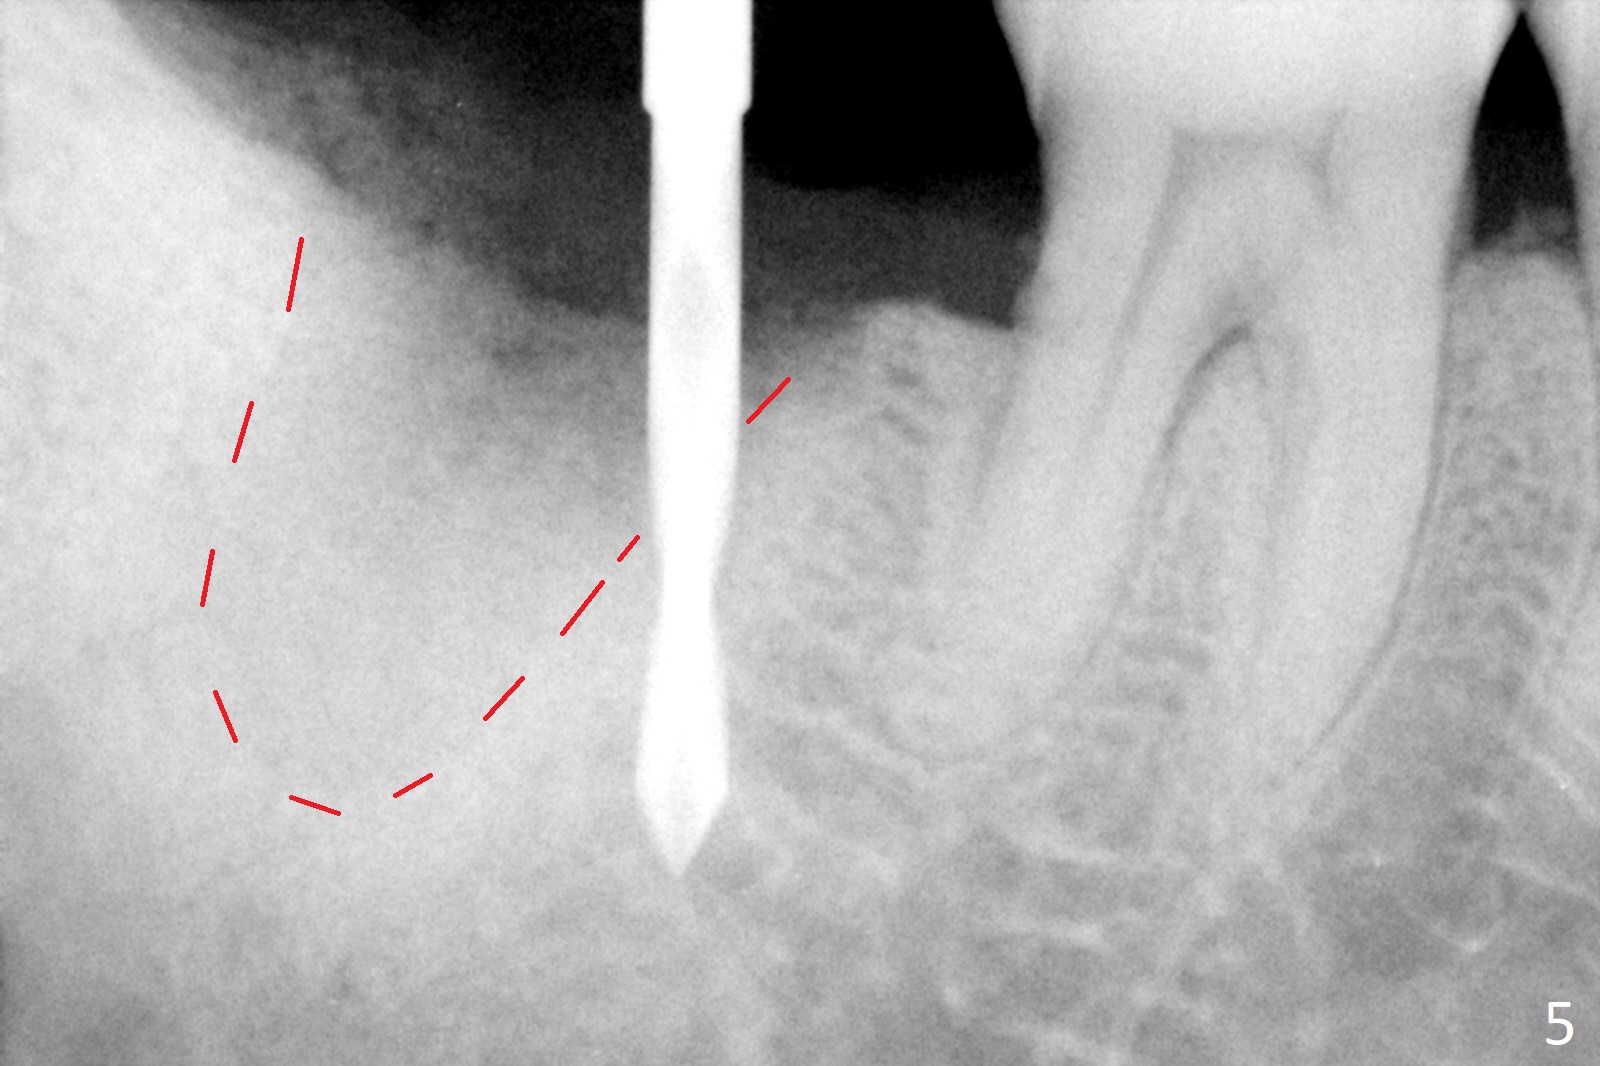

A 50-year-old man, a smoker, presents to clinic with pain of the tooth #15 with apparently occlusal trauma (Fig.1). Two years and three months after #15 extraction, he returns for #31 extraction (Fig.2) and socket preservation (Fig.3). The socket depth is 17 mm along the long axis of the socket 2.5 months post extraction (Fig.4, gingival level). Initial osteotomy is created in the mesial slope of the socket for 14 mm (Fig.5). After sequential osteotomy, a 6x17 mm tap is seated shallower (Fig.6) than the 2 mm drill (Fig.5). Following further osteotomy, a 7x14 mm implant is seated incompletely (Fig.7), which was not found intraop. The implant becomes loose with purulent discharge 19 days postop. The patient returns for 2nd placement 2 months post implant removal (Fig.8). Osteotomy is created probably in the mesial slope with 17 mm (bone level, Fig.9). After insertion of 5 (Fig.10) and 6 (Fig.11) x20 mm taps (tissue level), a 6x20 mm tissue-level implant is placed with clearance from the Inferior Alveolar Canal (Fig.12 yellow dashed line). The implant is restored 8.5 months postop (Fig.13) without bonding 5 mm 0 degree unipost. The crown dislodges 4 months post permanent cementation. Still the patient complains of small crown without occlusal contact. Impression is taken for a new normal-sized crown. The new crown becomes loose 1 year 9 months post cementation (Fig.14). The teeth #14 and 15 remain unrestored.